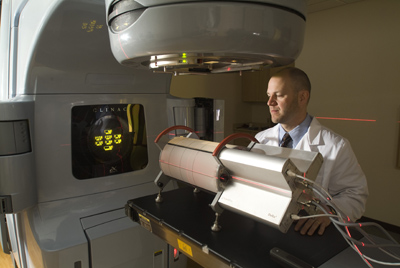

Annual Linear Accelerator QA

In today’s busy, cost conscious oncology practice, performing the annual linear accelerator QA can be burdensome for the on-site physicist as well as costly to maintain the expensive equipment needed to perform this important quality assurance.

OMPC has the right equipment in order to perform all testing required by the AAPM and ACR for annual evaluation. Our equipment is designed to be portable – alleviating the need for your facility to purchase expensive equipment that is just used once a year! The following tests are performed during an annual evaluation:

Specializing in commissioning of Varian linear accelerators and Eclipse treatment planning systems as well as RapidArc® treatment delivery, OMPC can free up the on-site physicists time and collect data and commission the systems fast to get you started with your new machine as quickly as possible.

Using the portable PTW scanning water tank system, staff of OMPC has performed many linear accelerator acceptance and commissioning projects. In just 2 weeks, your new linear accelerator and treatment planning system can be commissioned for use for conventional AND IMRT treatments. RapidArc® commissioning is performed in 2 days so that you can utilize this phenomenal new treatment modality as quickly as possible.